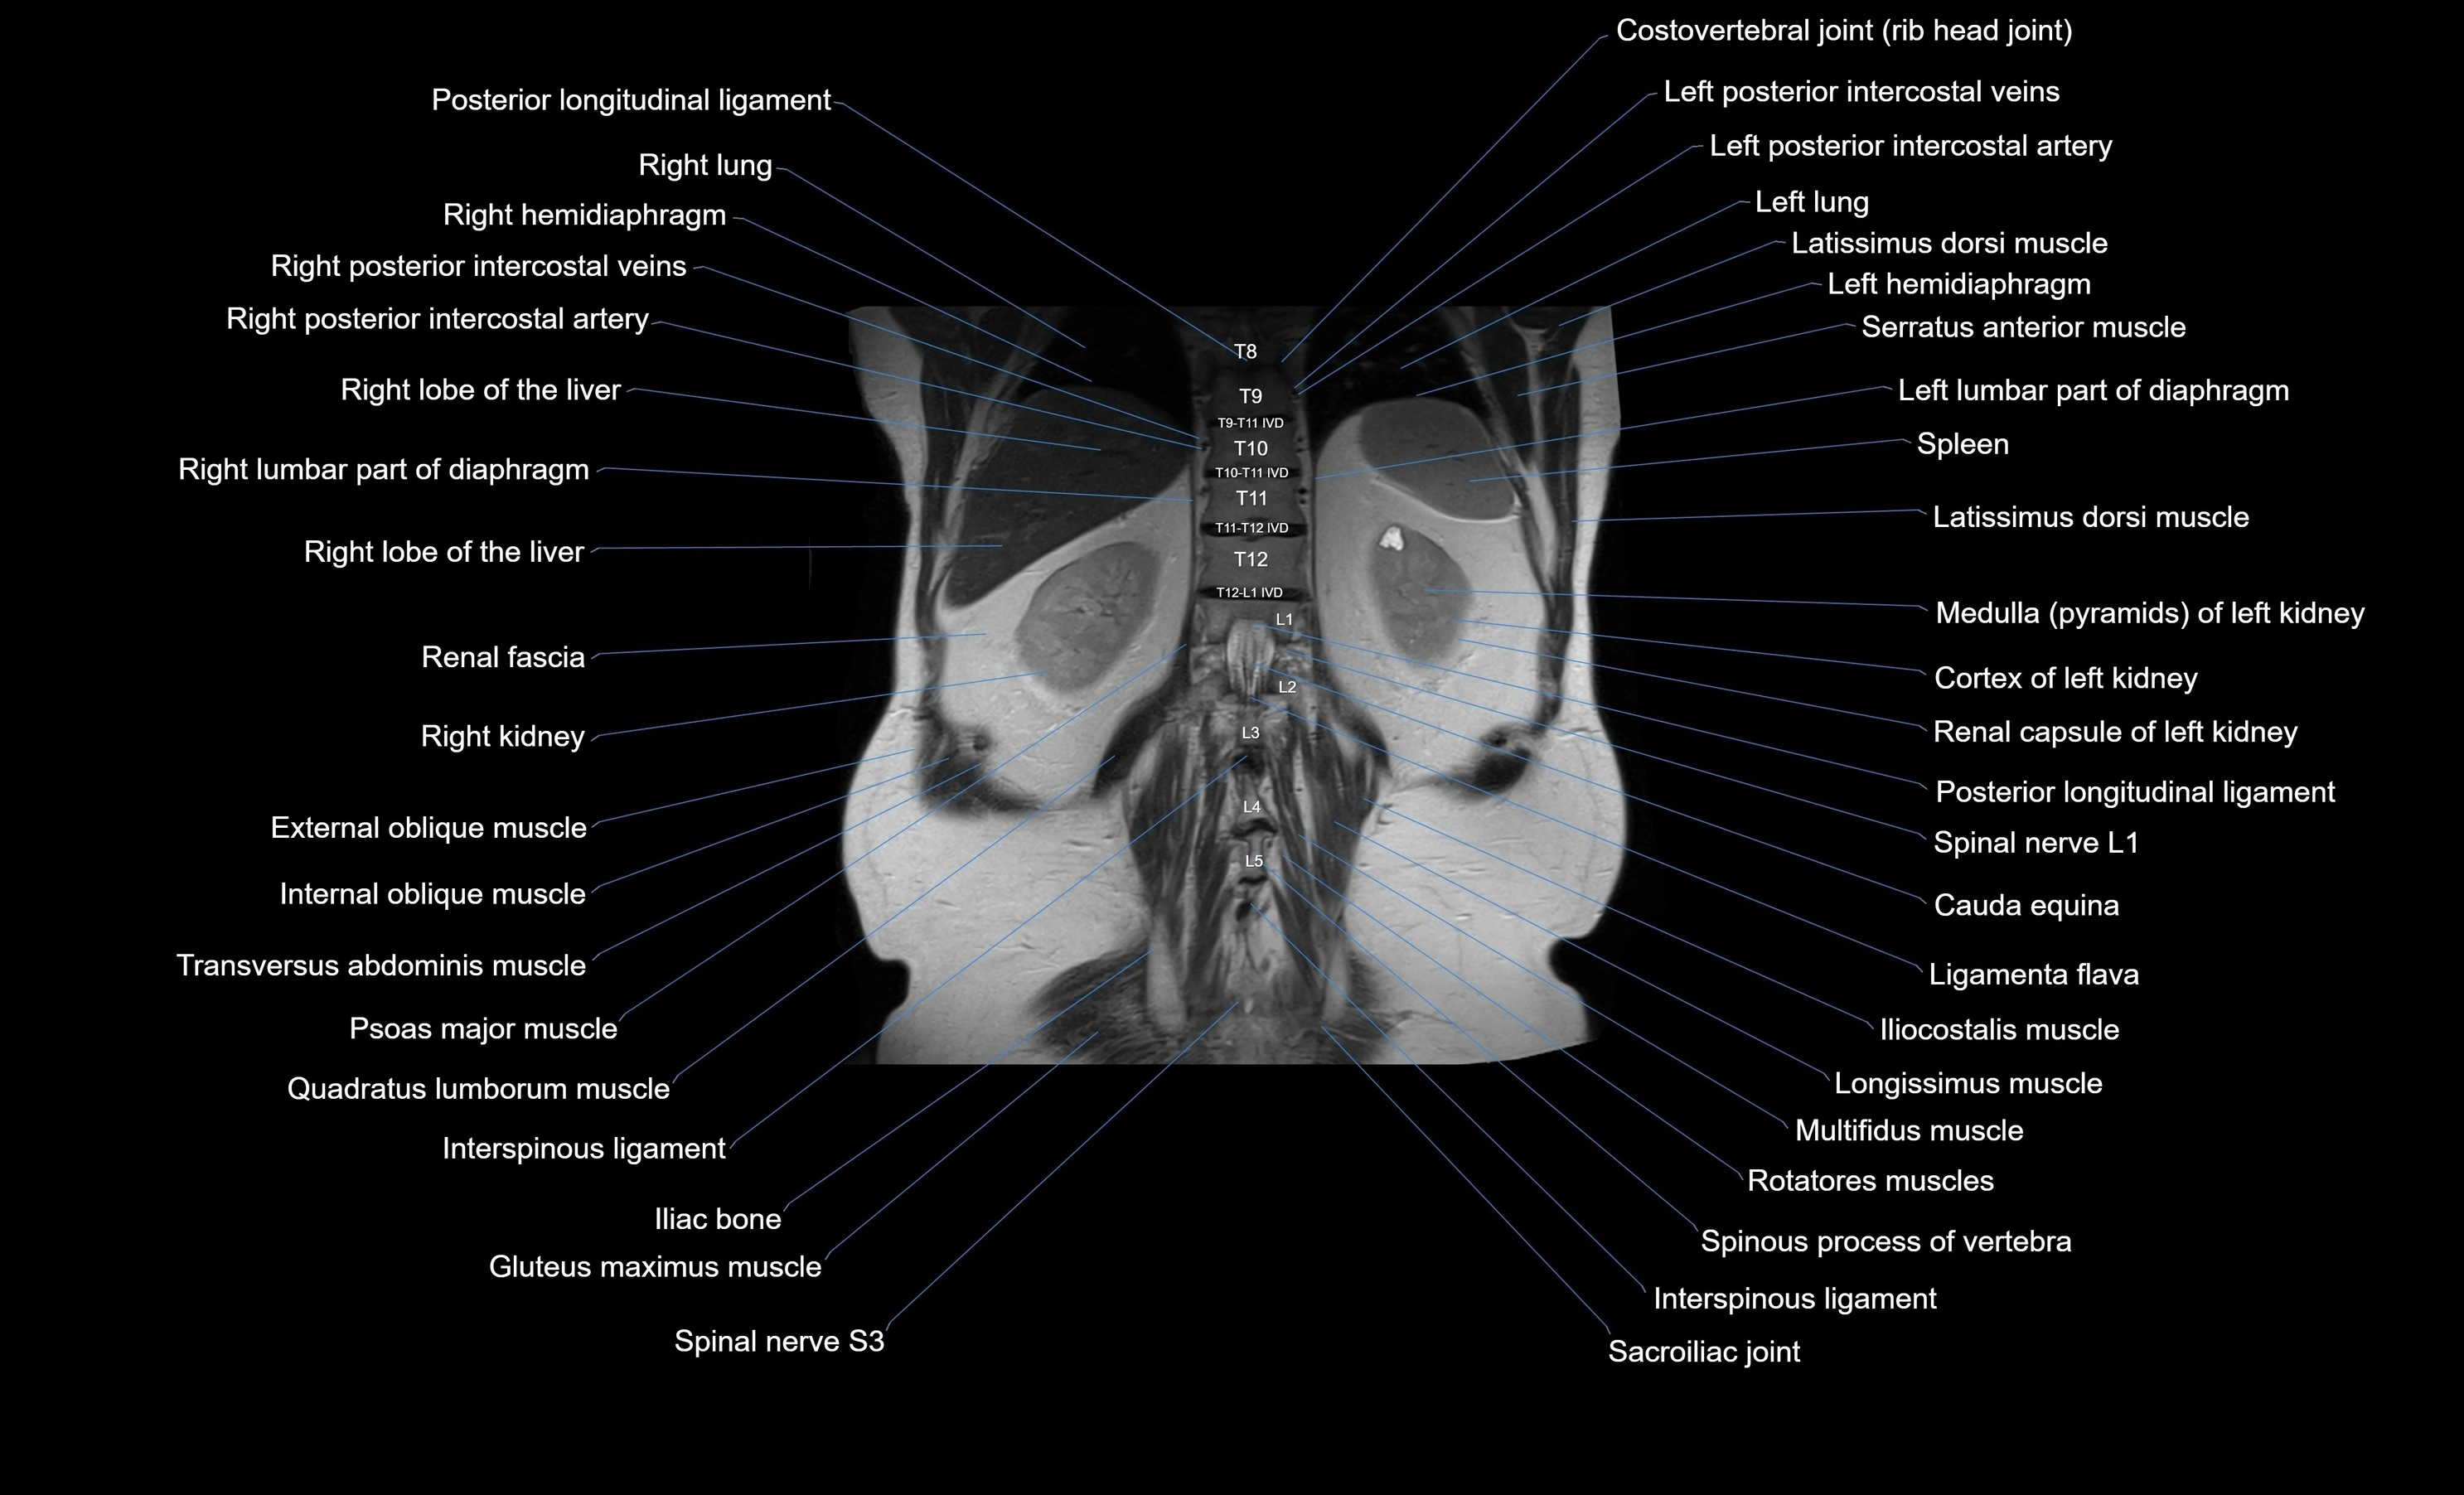

- Cauda equina

- Left kidney

- Renal fascia

- Right kidney

- Right lumbar part of diaphragm

- Rotatores lumborum muscles

- Rotatores muscle

- Spinal nerve L1

- Spinal nerve S3

- Spleen